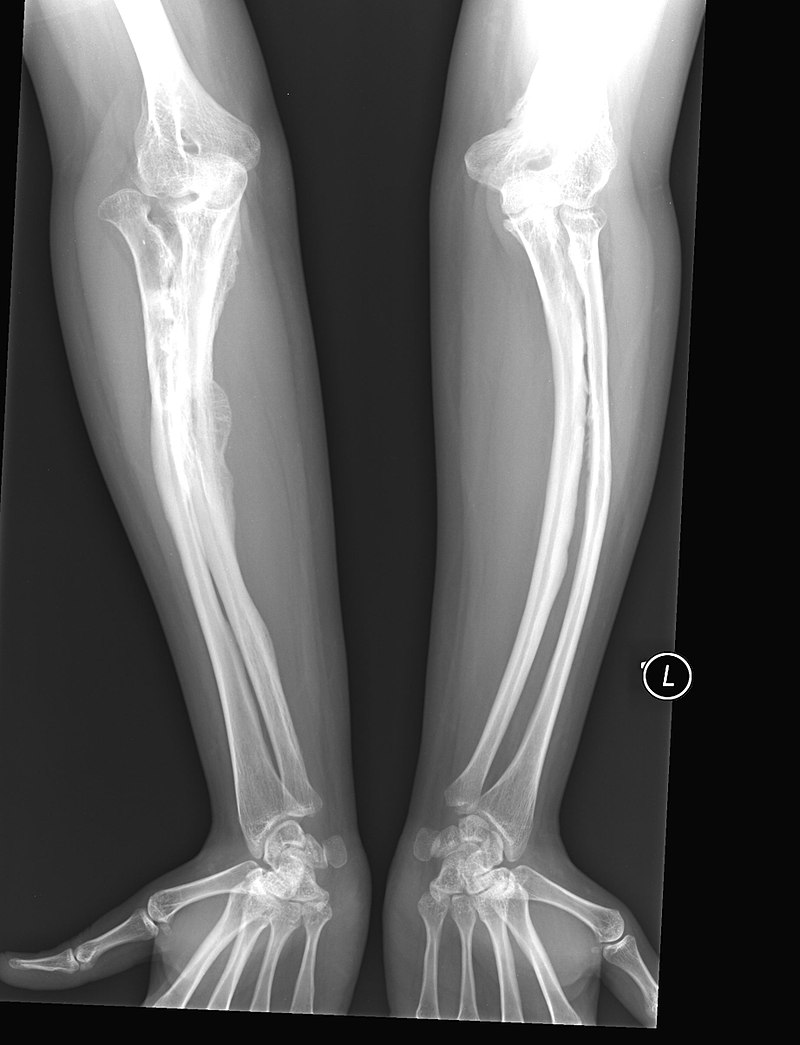

Osteogenesis Imperfecta (OI)

Osteogenesis imperfecta (OI) is a congenital bone resorption disease that results in structurally weak bone.

Osteogenesis imperfecta (OI) is caused by an autosomal dominant defect in collagen type I synthesis.

Clinical symptoms of osteogenesis imperfecta (OI) include:

- Blue sclera

- Hearing loss

- Multiple fractures of the bone

Note that the middle ear bones are also prone to fracture in osteogenesis imperfecta (OI).